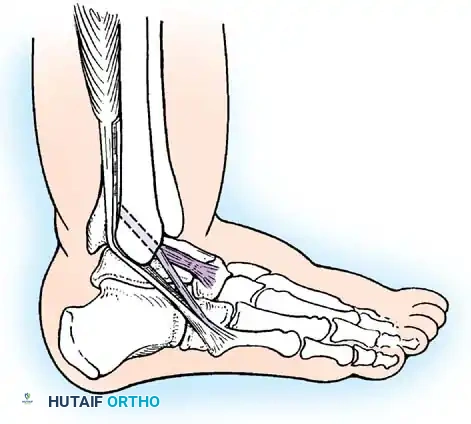

Repair of Acute Rupture of the Deltoid Ligament

Isolated surgical repair of the deltoid ligament is rarely indicated. However, in the setting of a bimalleolar equivalent fracture (fibular fracture with complete deltoid rupture and lateral talar shift), the deltoid may become incarcerated within the medial clear space, preventing anatomic reduction of the mortise.

Surgical Technique:

1. A medial longitudinal incision is made centered over the medial malleolus.

2. The joint is cleared of hematoma and the interposed deltoid ligament is extracted from the mortise.

3. The deep posterior tibiotalar ligament is repaired first using suture anchors placed into the medial talar body or medial malleolus.

4. The superficial deltoid is then imbricated and repaired in a pants-over-vest fashion.